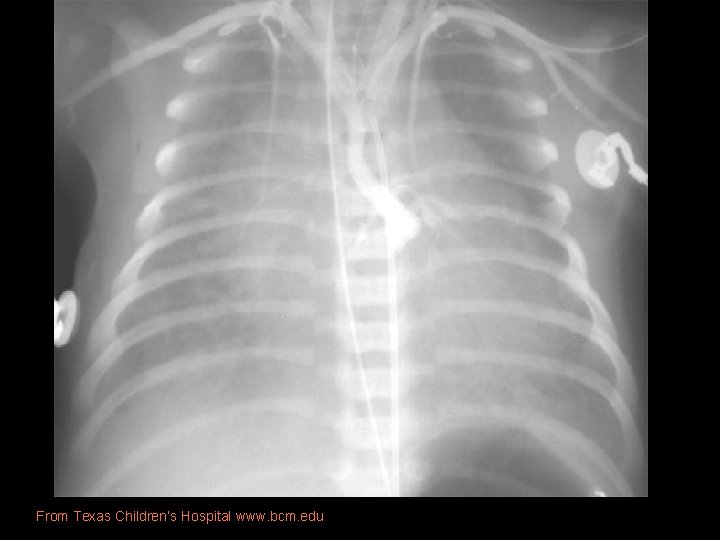

Imaging • Prenatal US: diastolic flow reversal in extremely narrow ascending Ao is diagnostic for HLHS. • Real-time echo: § sm, thick walled LV, sm MV w/restricted motion § Dilated RH/PA, lg PDA § Sm ascending Ao • CXR: § Moderate-marked CM § Globular cardiac silhouette suggesting combined chamber enlargement § PV congestion with interstitial/pleural fluid

From Texas Children’s Hospital www. bcm. edu